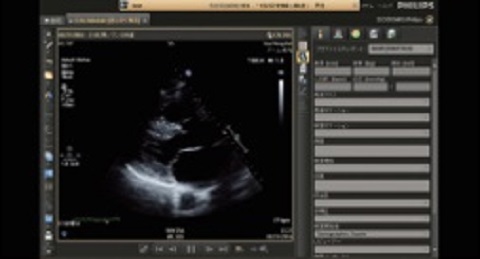

エコビューアを使用することで、超音波診断装置上で計測したDICOMストラクチャードレポートの情報のレポート取得や再計測、解析ソフトウェアが使用可能なため、検査の後でも超音波画像診断装置を占有せずに計測、解析を行うことができます。